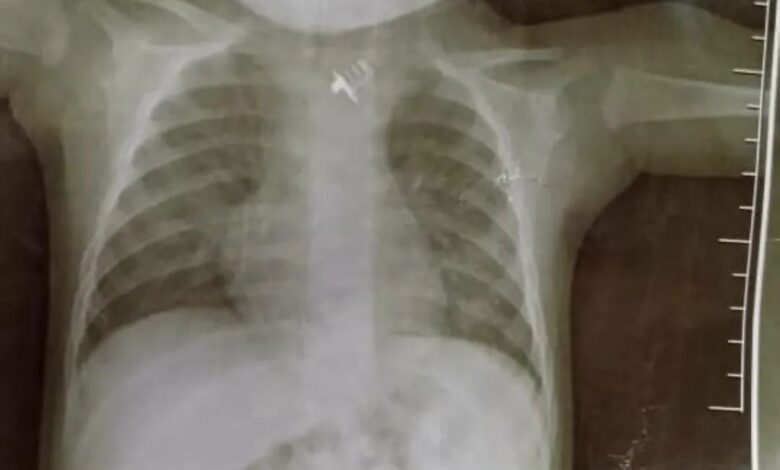

نجحت كوادر الطبية والفنية بمستشفى بن زيلع الحديث في إجراء عملية عاجلة لطفل يبلغ من العمر 6 أشهر ابتلع قطعة حديد من ريموت، مما تسبب له في عدم القدرة على الرضاعة أو الشرب لمدة أربعة أيام متتالية مع معاناة وبكاء مستمر

وباشرت الكوادر الفنية بالطفل لغرفة عمليات الكبرى بإشراف الدكتور عمر حسان – أخصائي الأذن والأنف والحنجرة – حيث تمت العملية بنجاح خلال وقت قصير .